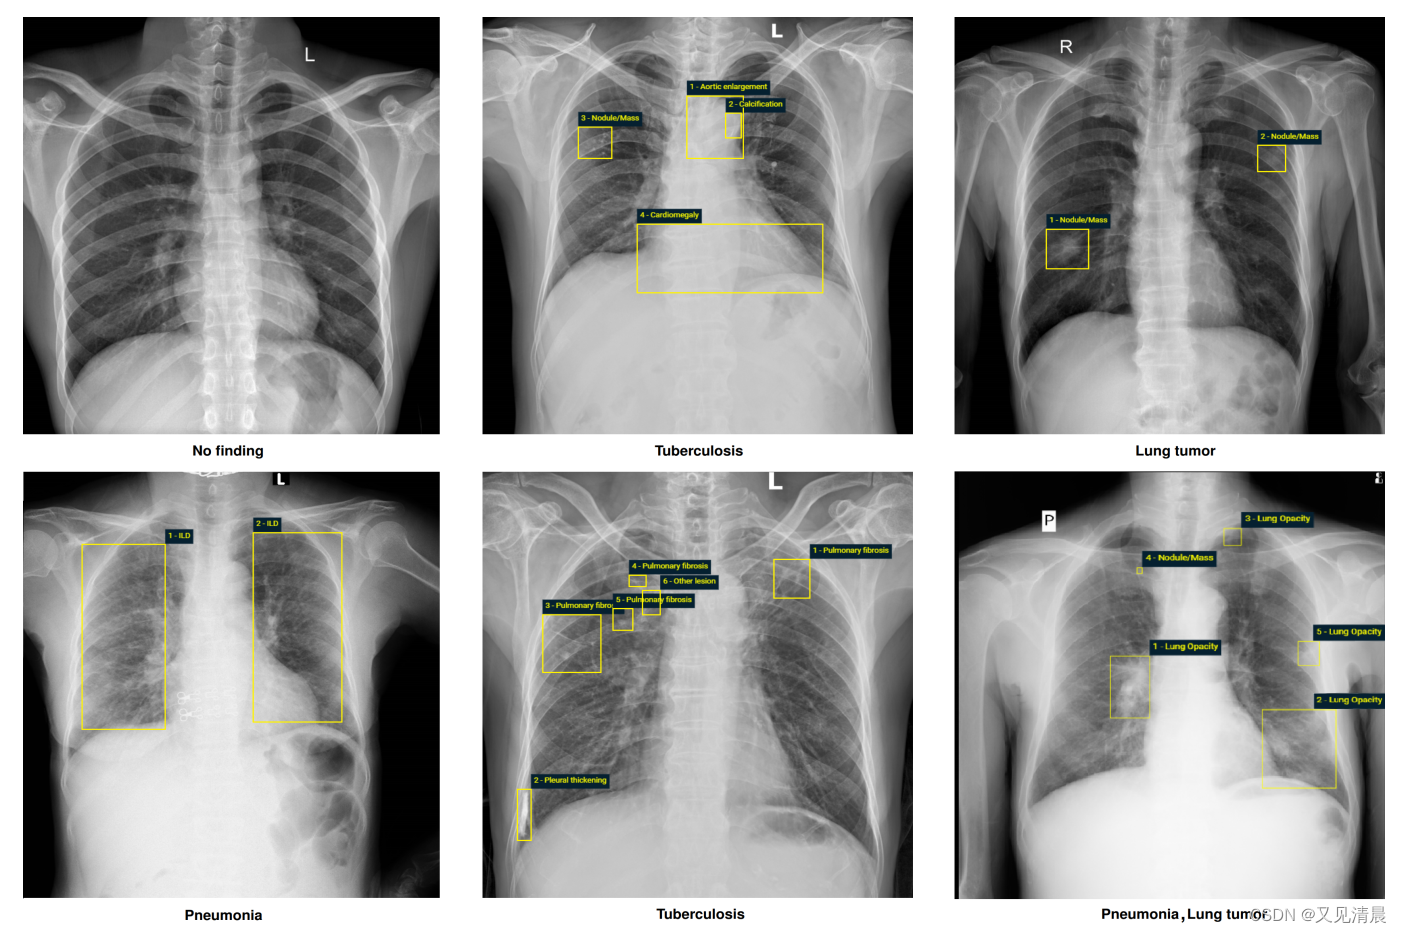

为了向研究界提供具有高质量标签的大型胸部x射线(CXR)图像数据集,vindr从108医院和河内医科大学医院(越南最大的两家医院)收集的100,000多张DICOM格式的原始图像中构建了VinDr-CXR数据集。公布的数据集由18,000个前后(PA)CXR扫描组成,这些扫描带有关键发现的定位和常见胸部疾病的分类。这些图像由一组至少有8年经验的17名放射科医生对22个关键发现(局部标签)和6个诊断(全局标签)进行注释;每个发现都用边界框来定位。局部和全局标签分别对应于标准放射学报告的“发现”和“印象”部分。

vindr将数据集分为两部分:15000次扫描的训练集和3000次扫描的测试集。训练集中的每幅图像都由3名放射科医生独立标记,而测试集中的每幅图像的注释经过更仔细的处理,并从5名放射科医生的共识中获得。标记过程是通过我们自己的基于网络的框架VinDr Lab执行的,该框架建立在图像存档和通信系统(PACS)之上。